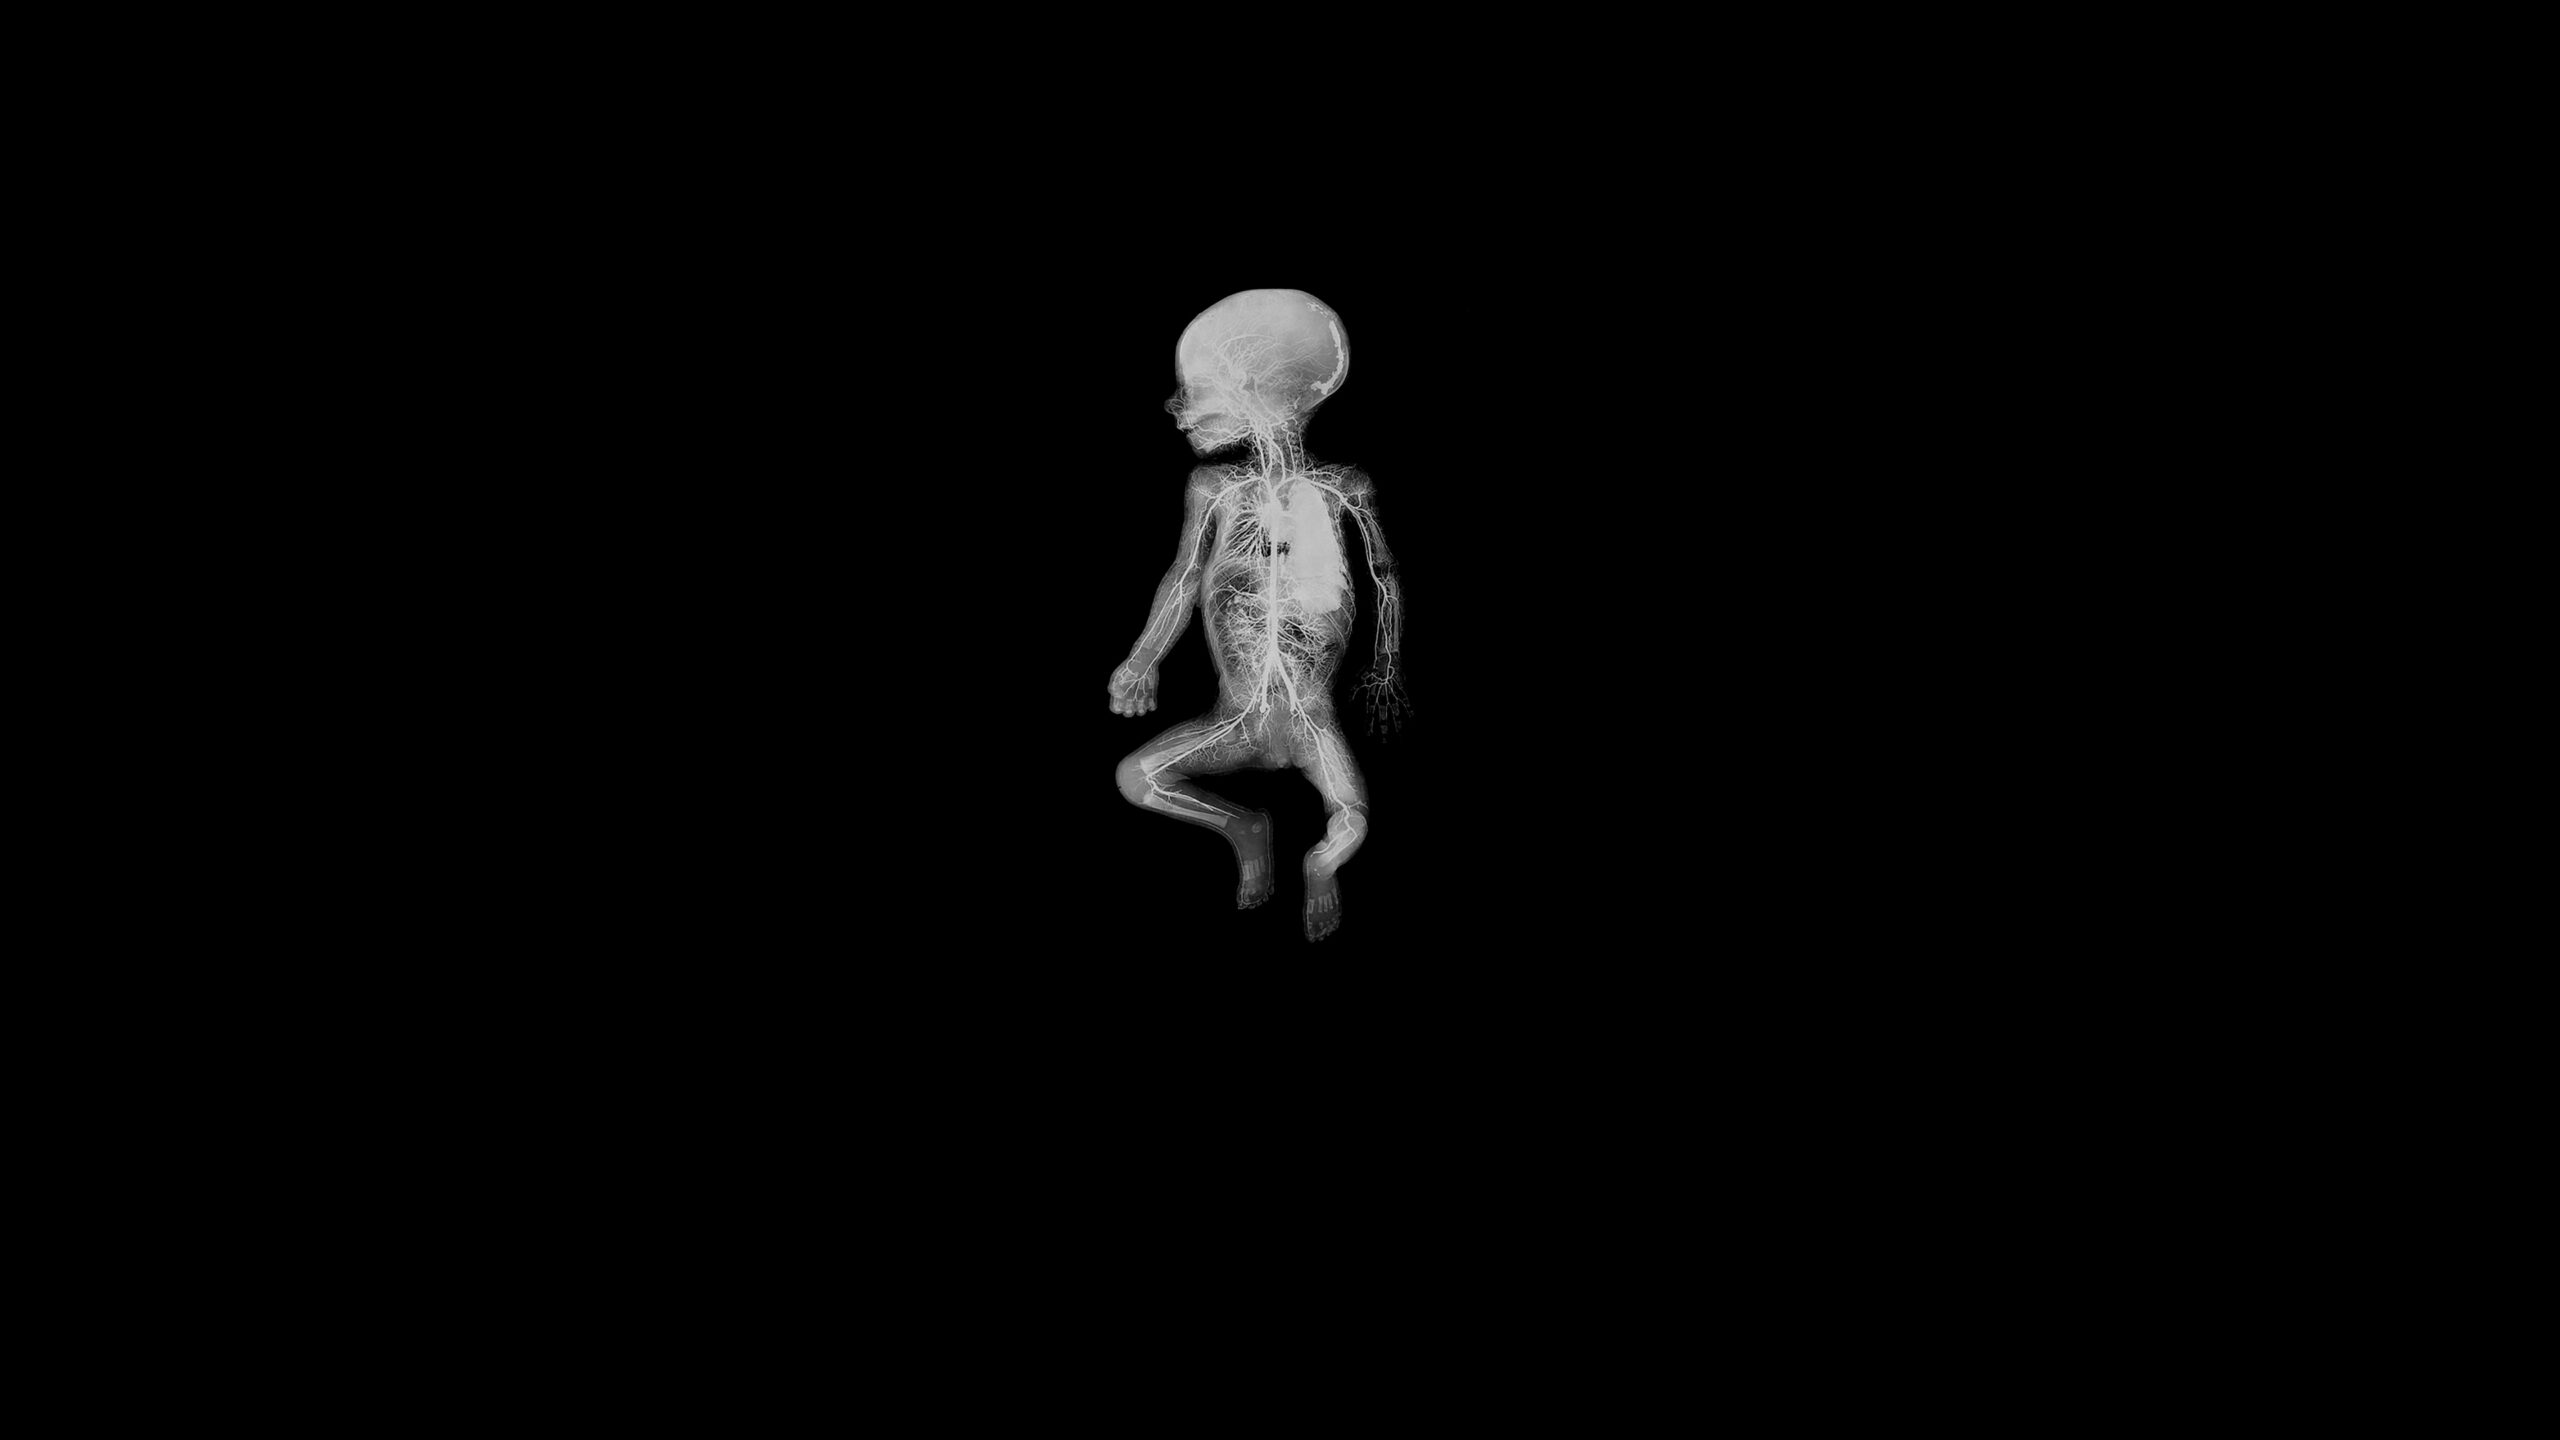

An extraordinary adventure through the interior of the human body; or the discovery of an alien landscape of unprecedented beauty.